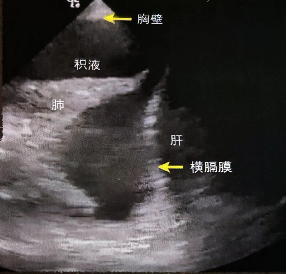

3. 胸腔积液

在二维超声图像中可看到“四边征”视频4,胸腔积液的四周由胸膜线(上界),肺(下界),两侧的肋骨影构成。M型超声下观察正弦曲线征图8,正弦曲线征表示浮动的肺随着呼吸朝向胸壁的运动,是胸腔积液的特征性表现。

探头类型及位置:相控型或凸阵探头,探头垂直皮肤,标记点朝向头侧。从L4区域远端开始,向头端滑动探头,寻找膈肌与胸膜(图9)

声像图表现:壁层胸膜和脏层胸膜,被低回声区分开。随着呼吸伴有肺运动(水母征)(图10,视频5)